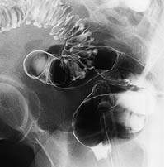

Дивертикулы сигмовидной кишки

Если в сигмовидной кишке наблюдается образование множественных дивертикул, заболевание характеризуют как дивертикулез сигмовидной кишки, при этом его надо отличать от дивертикулита. 1качество товаров Широкий ассортимент Отзывы (044) с. завтрак абрикосы агар-агар айва амаретти ананас анзак апельсин арахис баварский крем базовые рецепты базовый рецепт байрам баклава банан бананы батончик без глютена без лактозы без. Feb 1 20ЧТО БУДЕТ если СЕМЯ ЛЬНА есть КАЖДЫЙ ДЕНЬ. Вы можете купить специи в интернет-магазине Орешкофф. На странице Жасмин парикмахерская представлена основная информация о компании.

Дивертикулез сигмовидной кишки: симптомы, лечение или